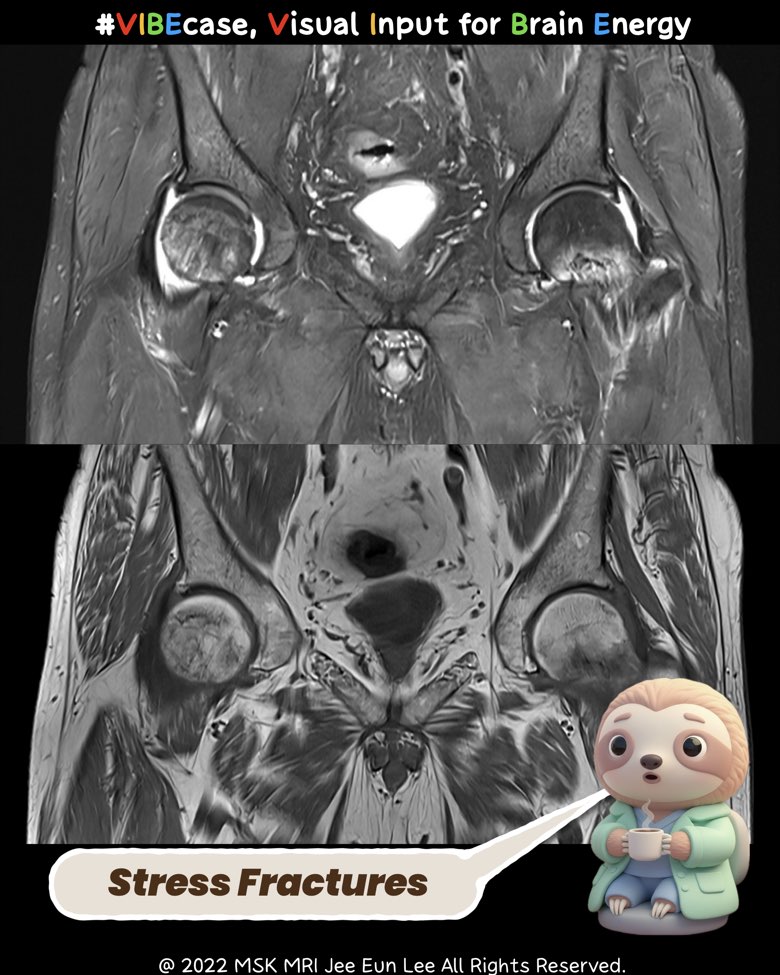

When the Cortex Is Intact but the Trabecula Collapses: Why Only MRI Reveals the True Injury

Cancellous (trabecular) stress injuries of the femoral neck and femoral head often remain completely invisible on CT.

The cortex stays intact, the subchondral contour appears normal, and the subtle attenuation changes fall below CT’s detection threshold.

MRI, however, shows the full pathophysiology:

1. T1-weighted MRI

- Irregular, wavy, crumpled low-signal trabecular lines

- No cortical break, no subchondral crescent line

2. T2/STIR / PD-FS

- Prominent diffuse marrow edema

- Serpiginous dark microfracture lines within the edema

- No double-line sign and no collapse (distinguishes from AVN)

3. Mechanism

A single compression-dominant stress overload affecting the inferomedial femoral neck and the weight-bearing dome of the femoral head, producing a continuous-spectrum trabecular injury.

4. Why CT Fails

- Cortex intact → no structural cue

- Microtrabecular collapse below CT spatial resolution

- Marrow edema undetectable on CT

- Subtle density changes obscured by noise and beam hardening

- Articular surface remains morphologically normal

Conclusion

CT stays “normal,” but MRI reveals the biologic truth.

This pattern is a classic CT-occult, MRI-diagnostic cancellous stress fracture.